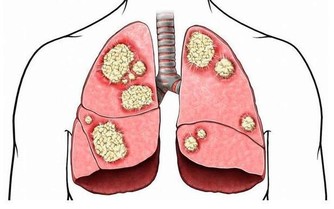

我們的大腦中有內分泌器官叫松果體,

它的主要功能是在夜間當人體進入睡眠狀態時,產生大量的褪黑色素。

這種色素在深夜11點至次日凌晨分泌最為旺盛,在天亮之後便會停止這些褪黑色素的分泌。

這不僅可以抑制我們人體交感神經的興奮性,還會導致我們人體血壓下降,心跳速度減慢,

使我們的心臟得到很好的休息,恢復體力,並能起到殺死癌細胞的作用。